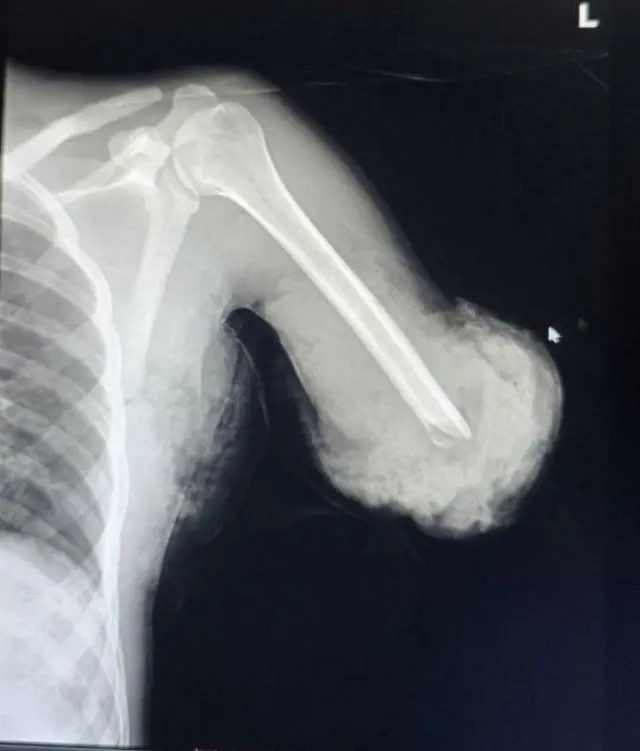

Dr. Anteneh akka ibsanitti miidhamaan ganna 20 kun torban sadii dura maashinii mukaa hojjechaa osoo jiruu harki isaa muramee hospitaala seene.

"Harki isaa ciqileen gaditti cite. Harki isaa guutummaatti qaama isaa irraa adda bahee ture," jedha doktorichi.

"Garuu inni kun harki guddaan murameera. Mucaa fi harkisaa addaan ba'anii dhufan," jechuun ibseera.

Dabalataanis, baqaqsanii hodhuun of eeggannoo cimaa barbaadu kun marsaa lamatti raawwatame; baqaqsanii hodhuun jalqabaa sa'aatii jaha fudhate.

Baqaqsanii hodhuun lammaffaan torban lama booda kan raawwatame yoo ta'u, gara sa'aatii jahaa fudhate.

Kanaaf ogeeyyiin harka dhukkubsataa qaama isaa isa hafe waliin akka walitti deebi'u baqaqsanii hodhuu sa'aatii 12 fi hordoffii torban hedduu raawwachaa turaniiru.

Yeroo baqaqsanii hodhuu kanaatti xiyyeeffannoo guddaan kan kenname "lafee fi ujummoo dhiigaafi ujummoon dhiigaa yeroo walitti deebi'u walitti qaamni cite akka hin duune taasifameera. Ogeeyyiin ujummoon dhiigaa fi lafeen bakka isaanii erga ga'ee booda narvii fi ligamentiin yeroon akka kennamuu fi baqaqsanii hodhuu sadarkaa sadarkaan akka raawwatamu murteessan."

Lafeen cite erga deebi'ee maxxanee booda fayyuu akka danda'u kan dubbatan Dr. Anteneh, qaamni cite soorata akka argatu ujummoon dhiigaa deebi'ee akka walitti hidhamus ibseera.